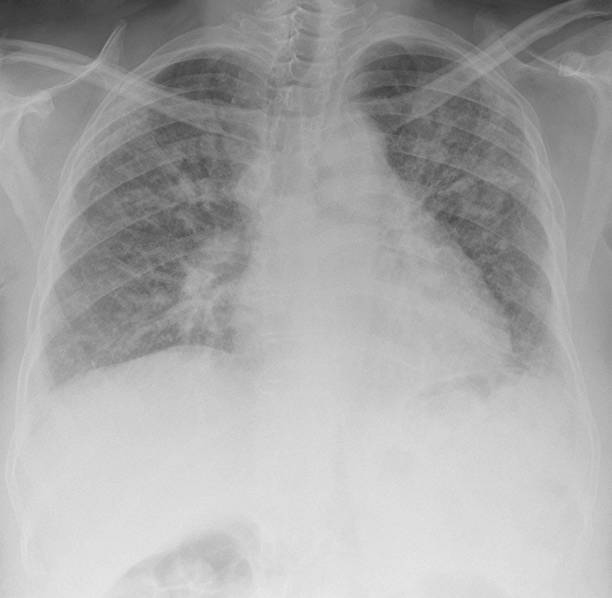

폐섬유화증은 폐조직 내 결손 및 염증에 의해 섬유화 과정이 일어나서, 건강한 폐조직이 염증과 섬유화에 대한 대체물질로 치환되는 질환입니다. 이로 인해, 섬유화된 조직은 신축성이 없고, 호흡기능이 저하됩니다. 따라서 다른 질병과 마찬가지로 초기에 적절한 치료를 받는 것이 중요하기 때문에 이번 시간에는 폐섬유화로 인한 증상들에 대해 정리해보겠습니다.

호흡 곤란은 폐섬유화증의 가장 대표적인 증상 중 하나입니다. 일반적으로 증상이 더해지는 것으로 나타나며, 물리적인 활동이나 감정적인 스트레스로 발생할 수도 있습니다. 호흡 곤란은 폐조직의 결손으로 인해 공기의 흐름이 제한되어 발생합니다. 호흡 곤란이 있을 경우 심한 경우에는 폐활량 감소로 인해 산소공급이 충분하지 않아 발생할 수 있는 산소부족증상에 의해 혼수상태에 이르기도 합니다.